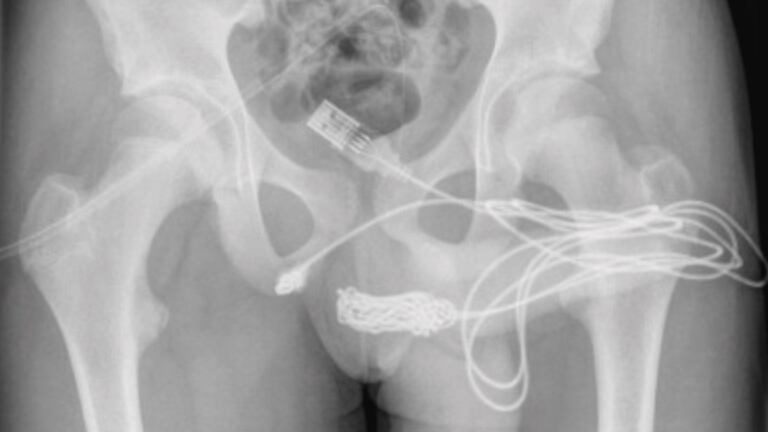

El caso quedó registrado por el portal Science Direct, en el que se explica que un joven de 15 años insertó el objeto de manera voluntaria como una forma de “experimento sexual”, para medir la longitud del miembro por dentro.

Según el reporte, el menor ingresó al hospital junto con su madre, experimentando fuertes dolores y con sangre en su orina. Al parecer, los repetidos y poco exitosos intentos que hizo de remover el cable, terminaron causándole complicaciones.

“Se descubrió que los dos puertos distales del cable USB sobresalían del meato urertal externo, mientras que la parte media del cable anudado permanecía dentro de la uretra”, se lee en el portal, en donde además se resalta que el paciente “era un adolescente sano y en buena forma física, sin antecedentes de trastornos de salud mental”.

Así, al llegar al lugar, el equipo médico realizó algunos procedimientos para intentar quitar el objeto, pero no resultaron eficaces. Por esto, tuvieron que someterlo a una cirugía y así poder acceder al cable.

Sobre la cirugía, el portal explica que “se realizó una incisión penoescrotal longitudinal sobre el cuerpo extraño palpable y se realizó una disección cuidadosa a través de los tejidos más profundos, dividiendo el músculo bulboesponjoso”.